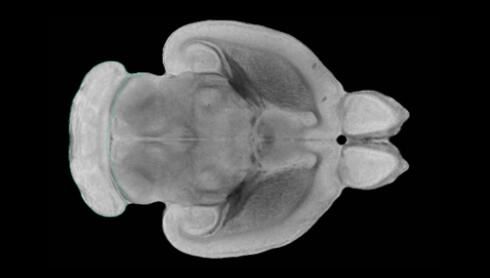

隨著機(jī)體年齡增加,肌肉和關(guān)節(jié)都會(huì)變得僵硬,這就會(huì)使得日常活動(dòng)變得更加困難,本文研究表明,我們的大腦也是如此,與年齡相關(guān)的大腦僵硬對(duì)大腦干細(xì)胞的功能或許有著重要影響。文章中,研究人員對(duì)年輕和老化大鼠的大腦進(jìn)行研究闡明了年齡相關(guān)大腦僵硬對(duì)少突膠質(zhì)前體細(xì)胞(OPCs,oligodendrocyte progenitor cells)功能的影響。OPCs是一類對(duì)維持正常大腦功能非常重要的大腦干細(xì)胞,其對(duì)于髓磷脂的再生也非常重要,髓磷脂是神經(jīng)組織周圍的脂肪鞘,在多發(fā)性硬化癥中髓磷脂的再生常常會(huì)被損傷,機(jī)體老化對(duì)這些細(xì)胞的影響常常會(huì)誘發(fā)多發(fā)性硬化癥的發(fā)生,這些細(xì)胞的功能在老化的健康人群中同樣會(huì)下降。

為了確定老化OPCs的功能缺失是否可以被逆轉(zhuǎn),研究人員將來(lái)自老化大鼠機(jī)體的老化OPCs轉(zhuǎn)移到了年輕大鼠柔軟的海綿狀大腦組織中去,值得注意的是,這些老化的大腦細(xì)胞能夠重新恢復(fù)活力,其行為非常像年輕更加強(qiáng)壯的細(xì)胞。這項(xiàng)研究中,研究人員在實(shí)驗(yàn)室中開(kāi)發(fā)出了具有可變僵硬程度的新型材料,并在受控環(huán)境下研究這些材料的生長(zhǎng)及其對(duì)大鼠大腦干細(xì)胞的影響,這些材料能被工程化改造具有和年齡或老化大腦相似的柔軟程度。

為了深入理解大腦組織柔軟和僵硬影響細(xì)胞行為的分子機(jī)制,研究人員對(duì)細(xì)胞表面一種名為Piezo1的蛋白質(zhì)進(jìn)行了分析,該蛋白質(zhì)能“告知”細(xì)胞其周圍的環(huán)境為柔軟或僵硬。研究者Kevin Chalut說(shuō)道,我們發(fā)現(xiàn),當(dāng)在僵硬材料上促進(jìn)年輕具有功能性的大鼠干細(xì)胞時(shí),這些細(xì)胞就會(huì)表現(xiàn)出功能異常,并失去其再生的能力,實(shí)際上其行為與老化細(xì)胞相似。當(dāng)將老化的大腦細(xì)胞在柔軟材料上生長(zhǎng)時(shí),其功能就會(huì)表現(xiàn)得像年輕細(xì)胞一樣,換句話說(shuō),其能夠重新恢復(fù)年輕的活力。